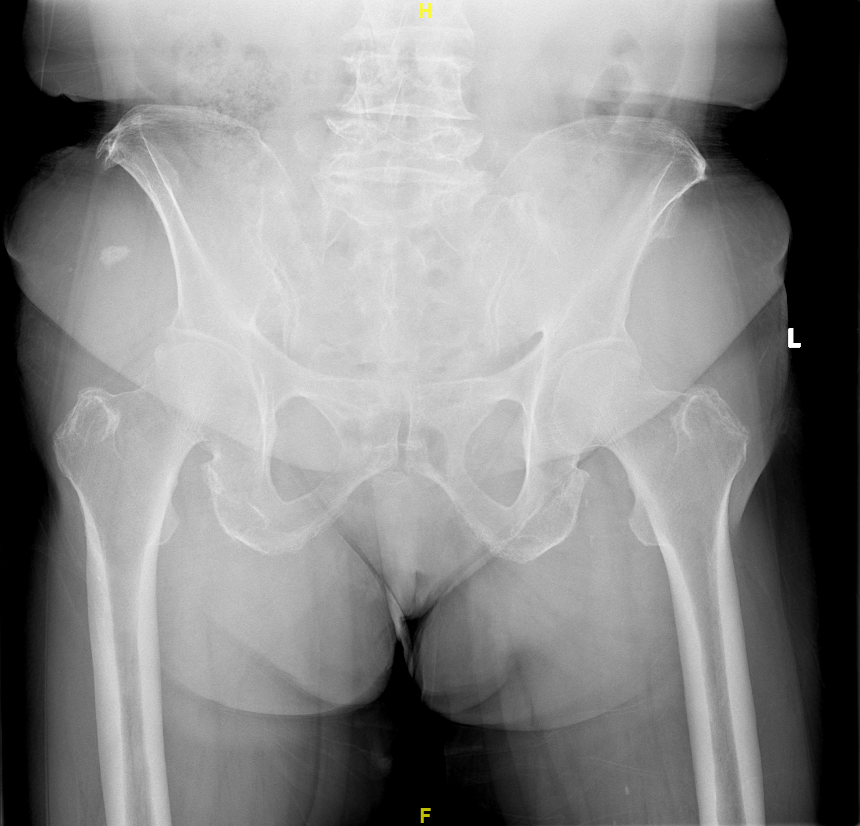

典型-双侧髋关节发育不良的X线片

上述两种方法是临床骨科最常用的髋臼发育不良(先髋,DDH)分型标准,大家可以对照自己的双髋关节正位X片,不难得出结果。当然面诊时,有经验的保髋专业医生,也会告诉您具体分型结论。

双侧髋关节发育不良-轻度-X线片,患者因双膝关节骨关节炎住院拟行膝关节置换手术治疗前,行双下肢全长正位X线片检查时发现髋臼发育不良(先髋,DDH),但查体和病史询问,患者无髋部疼痛症状,故不做任何治疗